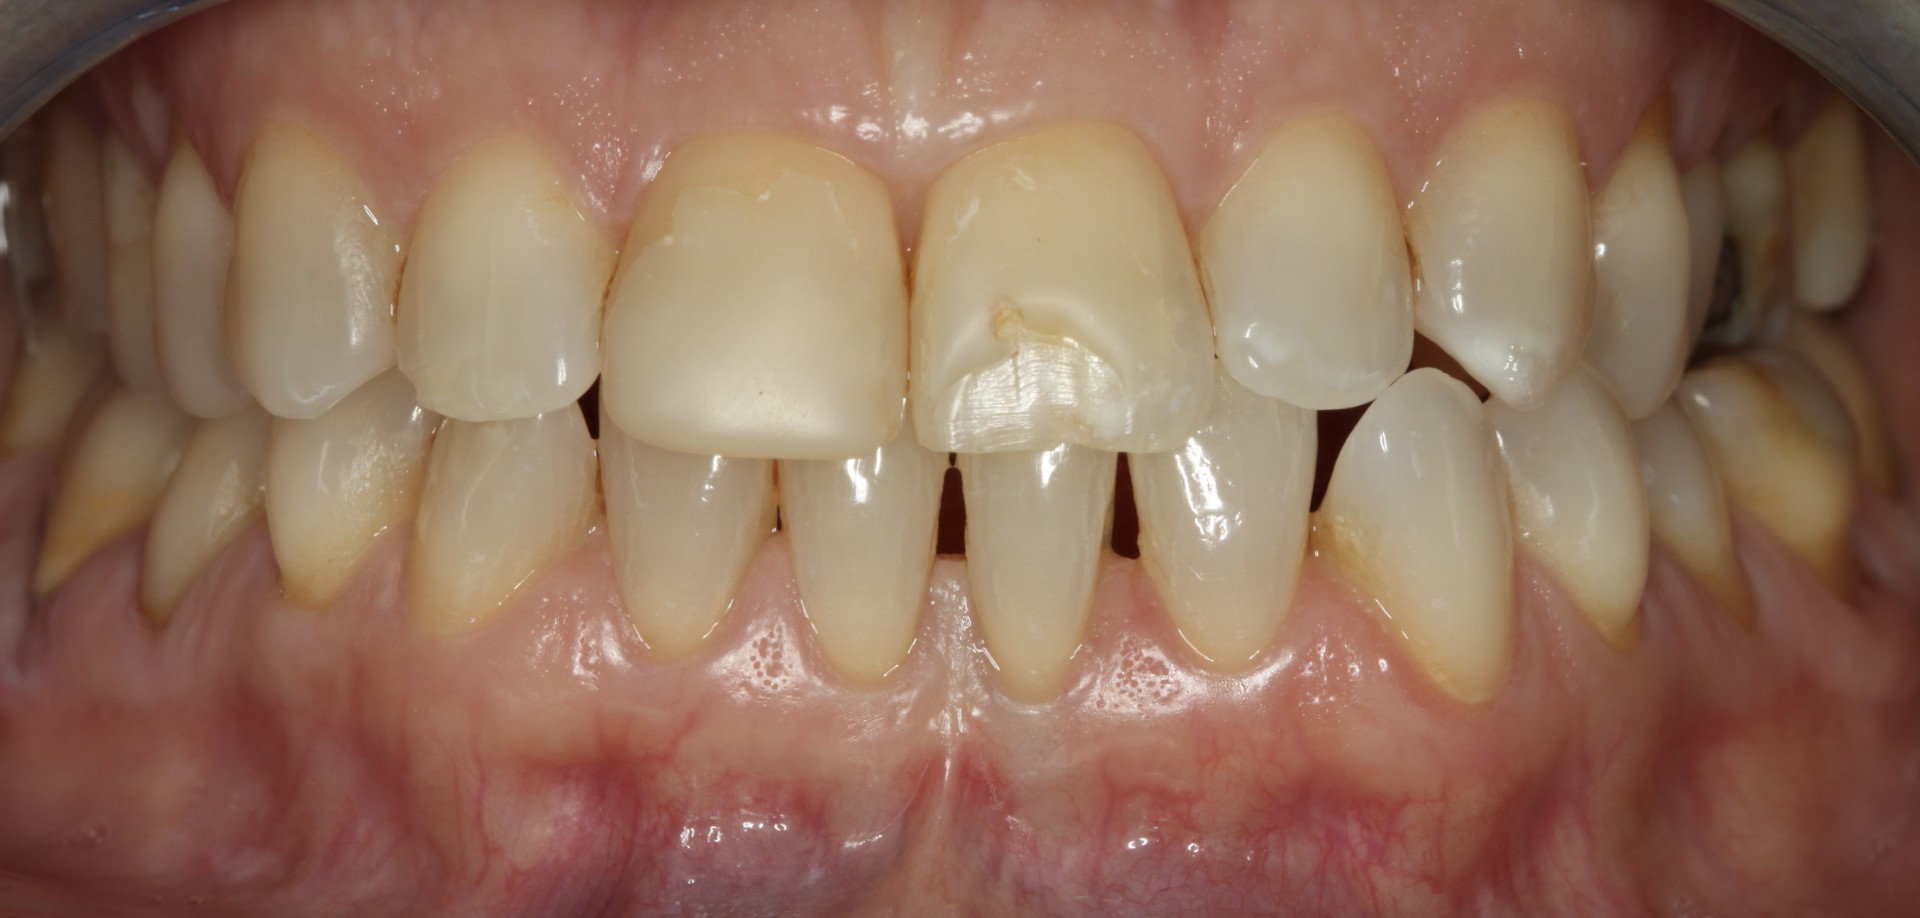

En este caso se combinan dos tratamientos el blanqueamiento y la carilla. La paciente tratada con blanqueamiento y carilla de composite a nivel de un incisivo central para mejorar el color y cerrar el diastema existente